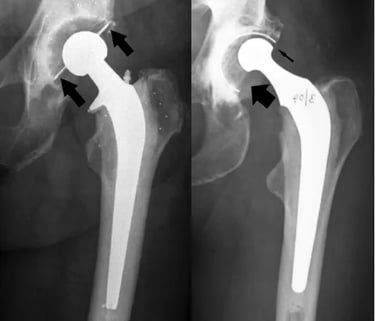

Em casos de desgaste do liner, ele identifica uma assimetria na espessura desse componente, uma vez que o desgaste ocorre na parte de cima apenas, conforme mostrado nas figuras abaixo. A primeira identifica uma prótese com polietileno normal e a segunda, uma com desgaste importante do liner.

Além disso, na presença de soltura da prótese, o RX também faz o diagnóstico, mostrando uma linha escura ao redor dos componentes da prótese (por conta da perda óssea nessa região) e/ou uma alteração do posicionamento dos componentes, quando comparado aos RX antigos

Essas imagens de RX são de modelos antigos de prótese de quadril, nas quais a qualidade dos materiais era muito inferior às disponíveis atualmente. Dessa forma, o desgaste nessas próteses era muito mais rápido e frequente, fazendo com que a durabilidade dessas próteses não fosse muito longa, em torno de 12 a 15 anos. Com o desenvolvimento das cabeças de cerâmica e liners de polietileno cross-linked, a durabilidade aumentou significativamente, para 25 a 30 anos.